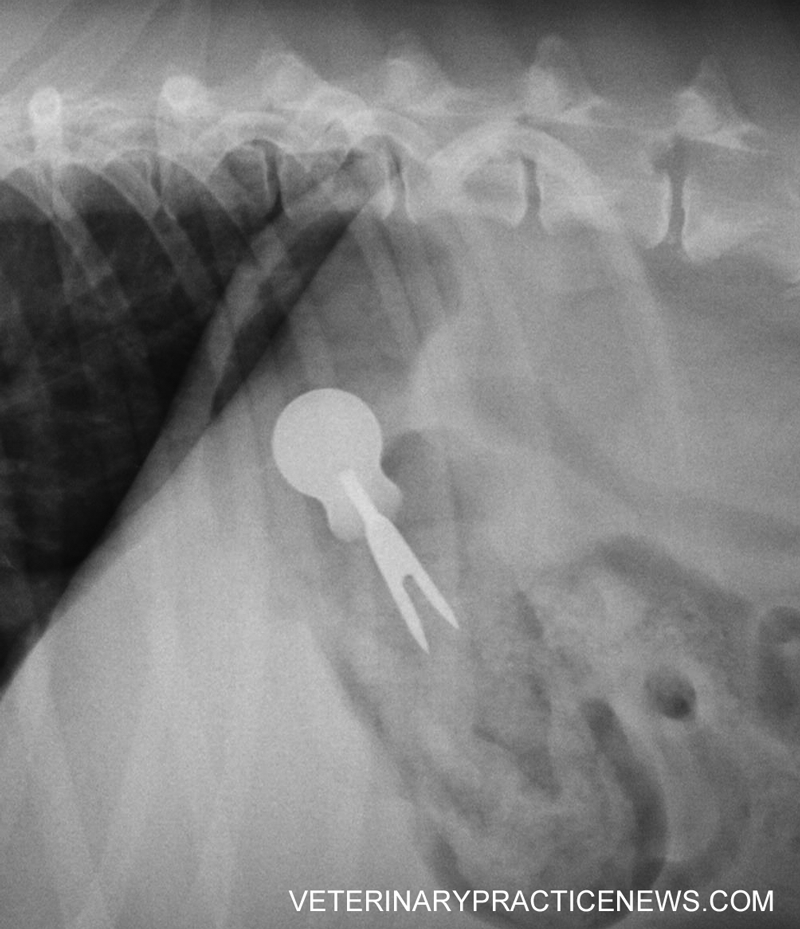

From www.veterinarypracticenews.ca

Revealed 2016 ‘They Ate What?!’ XRay winner Veterinary Practice News Canada Corn Cob Xray Dog Corn cob foreign bodies are common and frequently obstructive in dogs, especially during fresh corn season (summer to early autumn). They also absorb lots of liquid and can be abrasive to the intestinal lining. Trodorsal radiographs of a dog with a sock foreign body in the duodenum (arrowheads). Corn cob foreign bodies are common and frequently obstructive in dogs, especially. Corn Cob Xray Dog.